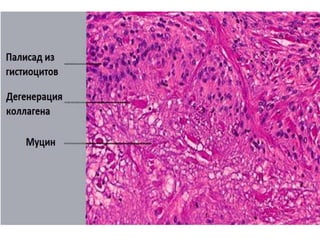

• При палисадниковой гранулеме мы видим клетки, окружающие

разрушенный коллаген (некробиоз), иногда муцин или инородное

тела в центре палисадниковой гранулемы.

• Кольцевидная гранулема имеет две формы

интерстициальную и палисадниковую.

• При интерстициальной форме виден муциновый

инфильтрат между коллагеновыми волокнами.

• При палисадниковом типе кроме этого мы видим

гранулемы с коллагеном в центре и в окружении

гистиоцитов.

• Главное отличие кольцевидной гранулемы от

липоидного некробиоза наличие муцина между

коллагеновыми волокнами при кольцевидной

гранулеме.